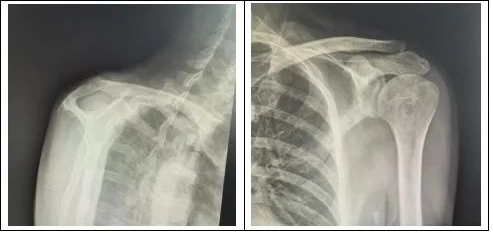

王先生的这两种肩关节疾病,治疗当中存在很大的冲突,冻结肩(肩周炎)需要在手术松解后尽早活动锻炼,而肩袖损伤需要在手术修补后进行一段时间的修养,在修养的这段时间里松解后的肩关节又会产生再次粘连的风险。